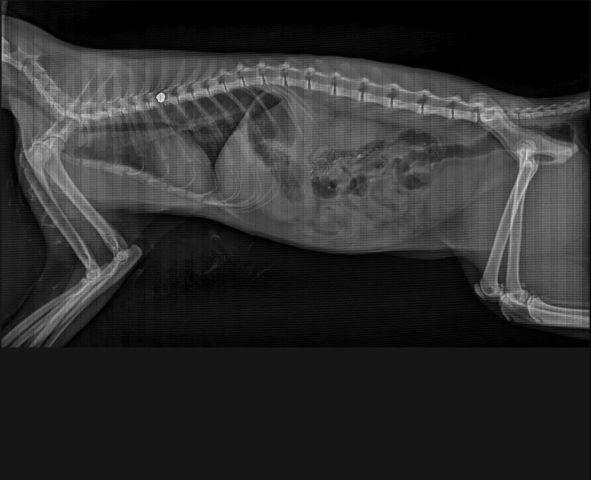

La protectora explica que, hace unos meses, encontró el cadáver de un gato con signos de violencia en el patio de un colegio de primaria; específicamente, el de Torrijos. Cinco meses más tarde, en el mismo centro, los niños alertaban a una de las cuidadoras sobre la presencia de otro gato en el patio, esta vez vivo, inmóvil, jadeante y muy asustado. Al trasladarlo al veterinario, se detectó la presencia de un perdigón alojado en su columna, el cual le había hecho perder la movilidad de las patas traseras. Ambos casos tuvieron lugar durante las horas lectivas, cuando el centro se encontraba lleno de niños. La asociación El Gato Garduño, como entidad colaboradora, asistió a los llamamientos.

Hace apenas unos días, una de las casas de acogida de esta misma asociación alertaba de la cojera de uno de sus felinos, el cual había salido al patio particular de su casa y regresado asustado y arrastrando una pata. Al ser revisado por los veterinarios, se encontró un balín alojado en ella. Actualmente, el animal está proceso de valoración veterinaria para determinar si puede conservar la extremidad.